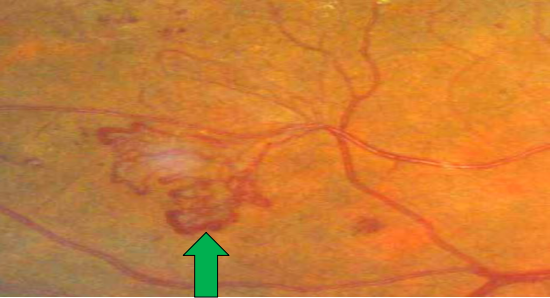

• I期(轻度):仅有毛细血管瘤样膨出改变,表现为边界清楚的红色斑点,大小一般不超过视盘边缘静脉血管直径,与组织缺血有关,是毛细血管以及毛细血管小静脉圆形膨隆状扩大,为DR的特征性改变,也是眼底镜下可见最早体征,可见于眼底任何部位。

• II期(中度):介于轻度与重度之间,合并视网膜出血、硬性渗出和(或)棉绒斑。其中硬性渗出为白色或黄白色沉着物,边界清楚且可融合成片,为血管通透性异常所致,是当前或既往发生黄斑水肿的表现;棉绒斑(软性渗出)为圆形或卵圆形白色、淡黄白色或灰白色病灶,边界不清、呈羽毛样;

• III期(重度):每一象限视网膜内出血≥20个,或至少2个象限静脉串珠样改变,或至少1个象限存在视网膜内微血管异常(IRMA),无新生血管形成。静脉串珠样改变表现为局限性血管壁扩张,有时聚集成串珠样形态。IRMA是增生前期改变,发生在无灌注区旁,为毛细血管床或吻合支的扩张部分,也可以是新发生的血管芽,眼底镜下呈树墩状或末端尖形扩张,在荧光素眼底血管造影下容易识别。

眼底检查可见微动脉瘤、出血斑点、硬性渗出、棉绒斑、静脉串珠状改变等典型体征。荧光素眼底血管造影可清晰显示眼底血管病变程度,为诊断提供重要依据。